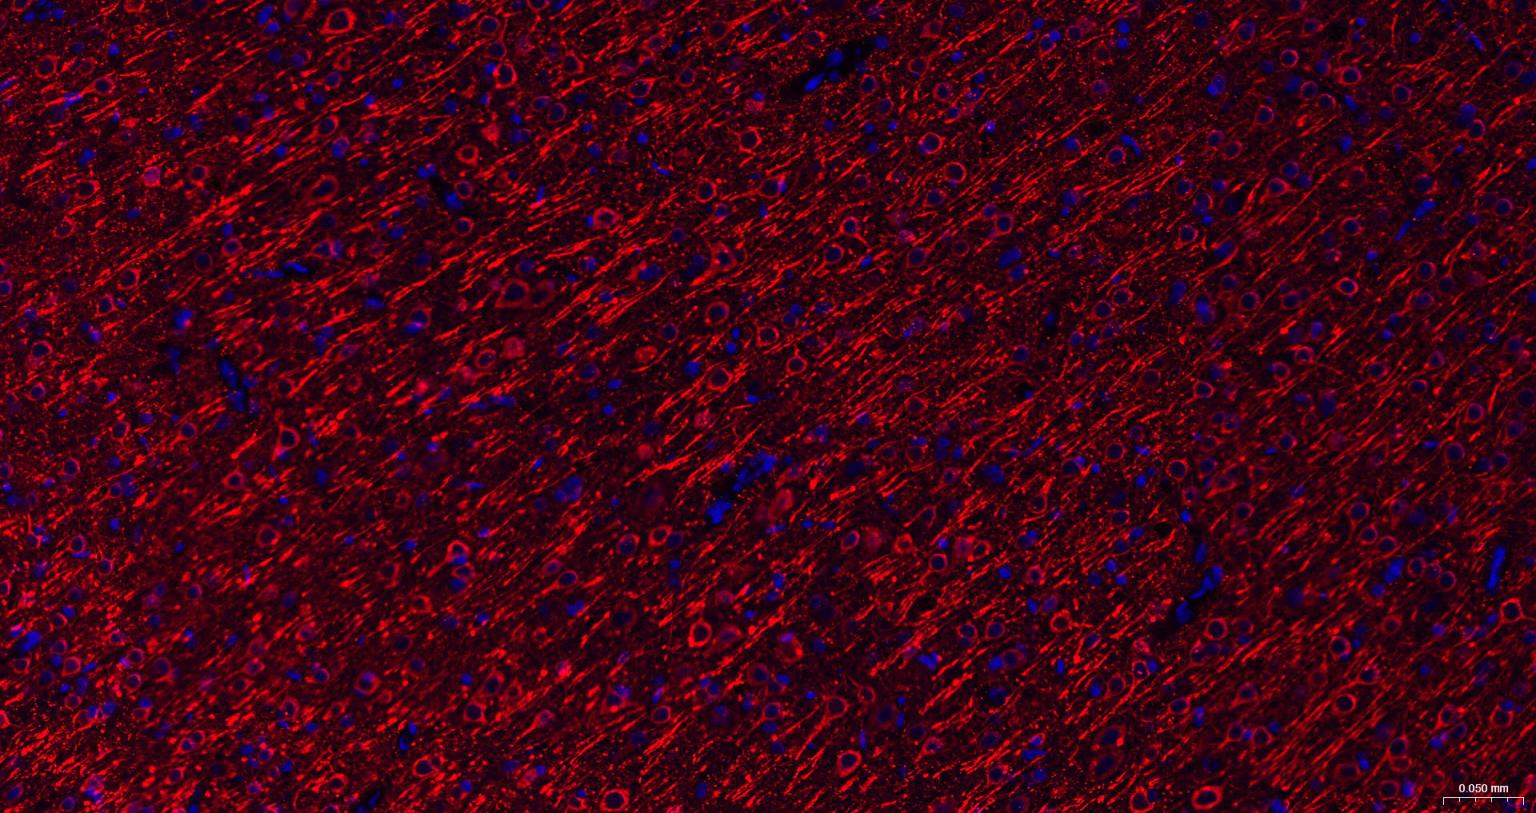

Paraformaldehyde-fixed, paraffin embedded Mouse Cerebrum; Antigen retrieval by boiling in sodium citrate buffer (pH6.0) for 15 min; The section was incubated with phospho-MAP2 (Ser136) Monoclonal Antibody, Unconjugated (bsm-62863R) at 1:200 overnight at 4°C. Followed by conjugated Goat Anti-Rabbit IgG antibody (Red, bs-0295G-BF594), DAPI (blue, C02-04002) was used to stain the cell nuclei.